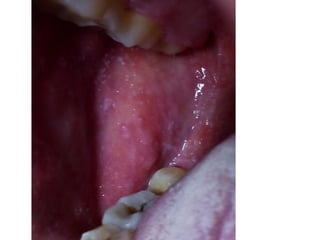

• Bé trai 10 tuổi. Nhập viện Phát ban N4

• N1. Sốt cao 40 độ, Nuốt đau họng, không ho,

không sổ mũi.

• N2: Nổi hạch góc hàm hai bên sưng đau, di

dộng.

• N3 phát ban và khám như hình chụp

• CLS: CTM BC 15 k/ml Neutro 78%. TC 230k/ml.

• CRP tăng 30 lần bình thường.

• Chứa từng bị tương tự lần nào.